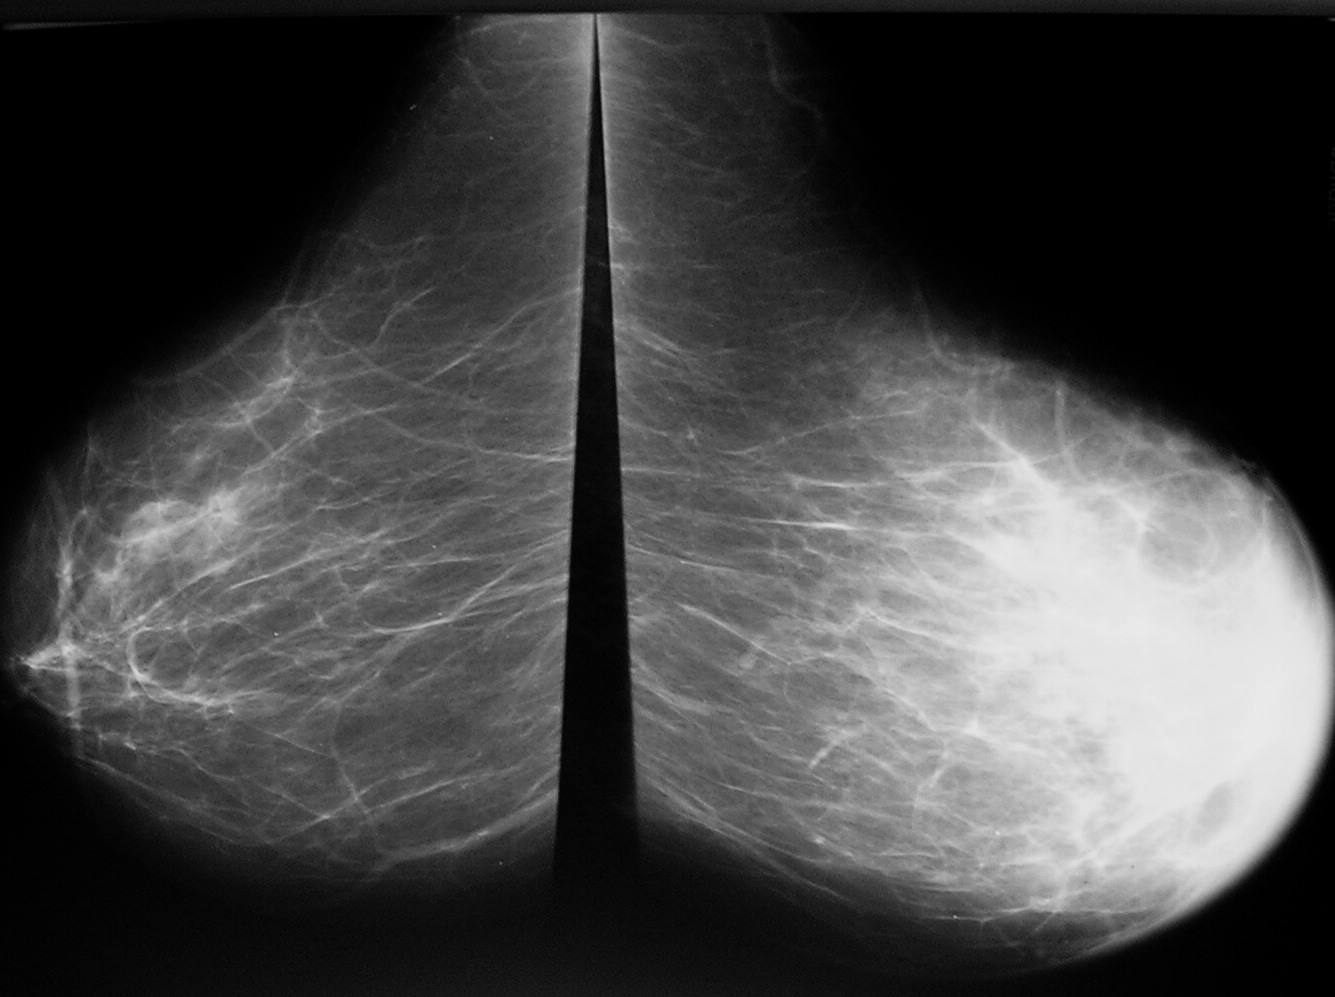

Фиброаденома молочной железы - доброкачественное образование, которое часто встречается у женщин. Оно может быть обнаружено при помощи различных методов диагностики, включая маммографию. Ниже представлены фотографии, помогающие понять, как выглядит данное заболевание.

Фиброзно-кистозная мастопатия рентген молочных желез

Фиброзно кистозная мастопатия маммограмма

Фиброзно кистозная мастопатия маммограмма

Маммография и ее роль в диагностике фиброаденомы молочной железы

Маммография - это рентгенологическое исследование молочных желез. Оно позволяет выявить различные изменения в тканях, включая фиброаденому. На маммограммах можно увидеть структурные особенности опухоли и отследить ее динамику во времени.